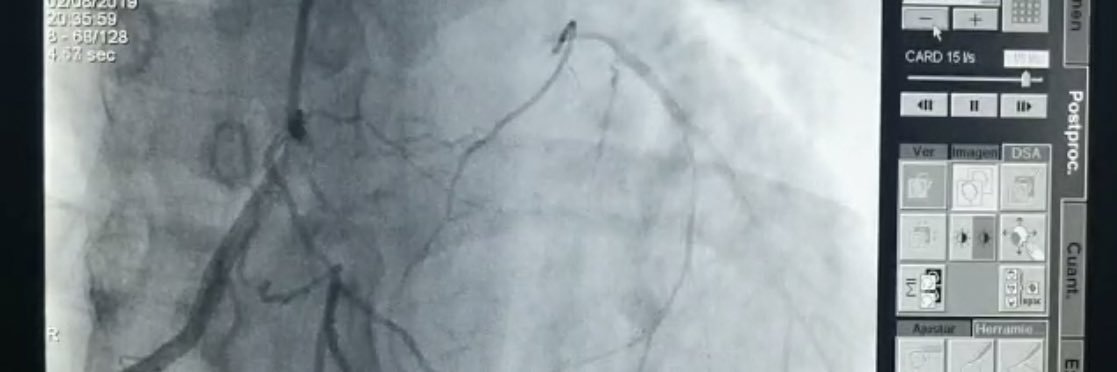

M 73, heavy smoker, unstable angina, Tn negative, CCS class 3 effort angina, single focal lesion, this! With small ball mobile thrombus, #RadialFirst Poll in

🧵